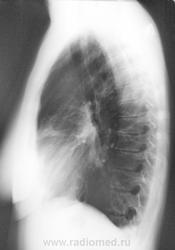

Осумкованный плеврит? в заднем отделе левого синуса.Так ли это?

Собираюсь на консультацию к кардиологу и сегодня сделала рентген в 2 проекциях. И Врач-ренгинолог меня просто ошарашил дословно: Осумкованный плеврит? в заднем отделе левого синуса.

Однозначно, что именно "осумкованного плеврита", в данном случае нет. Однако архивчик есть, да и верхушечки внимания требуют.

Вероятно левосторонняя пневмония в 3-м сегменте.

Здрасти . У вас по снимкам легочный рисунок резко усилен с обоих сторон , справа корень расширен и деформирован .Слева в синусе похоже небольшое количество жидкости ,но насчет осумкованности я сильно сомневаюсь . Вы анализы сдавали ? СОЭ, лейкоциты ..... Верхушки чистые , но вот справа корень и легочный рисунок мне не нравтся , да и что может вызвать выпот в плевральную полость . Было бы хорошо если бы вы сделали манту